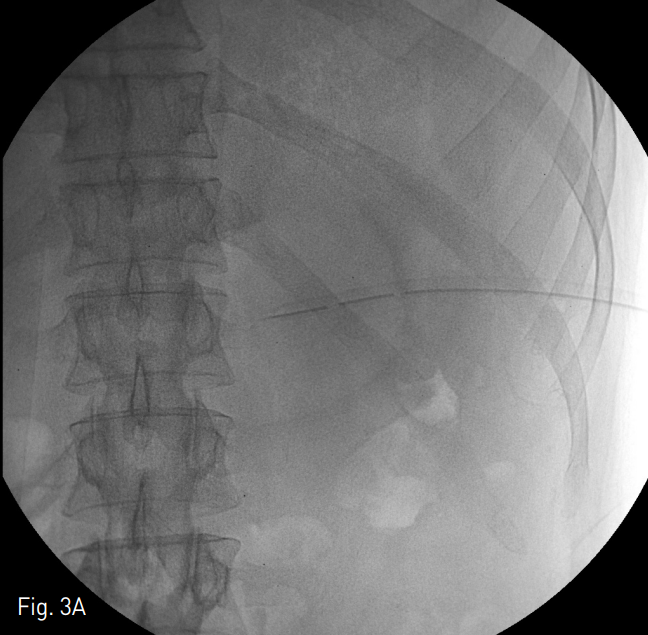

Fig. 3

The patient underwent massive saline irrigation (average total volume of normal saline: 8000cc) and aspiration necrosectomy using 50cc enema syringes. Procedure was performed eleven times in two months (A). Decreased extent of contrast accumulation at fluid cavity compared wi th ini tial fluoroscopic image (B).